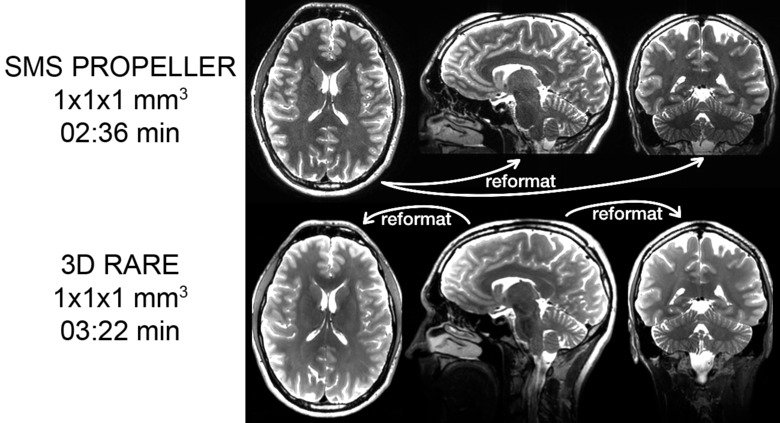

Motion robust pulse sequences - Accelerated pseudo 3D PROPELLER

There is a clinical need for 3D RARE images with isotropic voxels that can be reformatted into several different planes, it increases the information for the radiologist and facilitates the review of the images. The sequences typically used to collect these 3D data sets require long echo trains, which makes them sensitive to movement and also leads to so-called "T2 blurring". In order to provide these reformatable volumes for patients who cannot lie still, we have developed a movement-robust alternative. A sequence that, through a combination of SMS acceleration, thin slices, and a PROPELLER acquisition, can obtain images with the same qualities as its 3D counterpart, but at the same time can withstand large head movements.